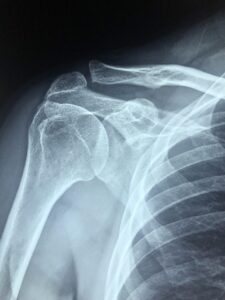

X-rays, ultrasounds, CT scans, and MRIs are some of the most common medical imaging tools used to help diagnose injuries and medical conditions — especially those involving the muscles, joints, and bones. They can be incredibly valuable in confirming a diagnosis or ruling out serious issues.

This principle applies to other joints too — it’s not unusual for shoulder, spine, or hip scans to show “abnormalities” that don’t actually cause pain or limit function.